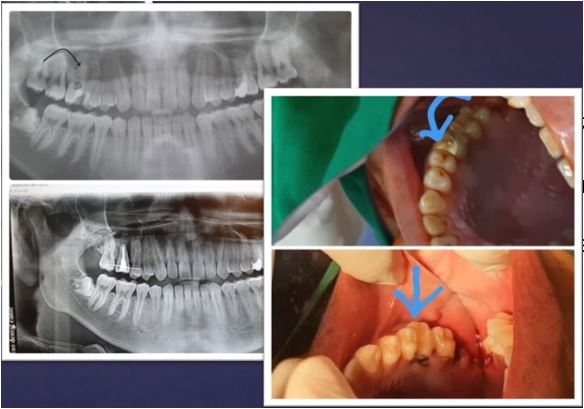

2020 онд манай ОРГИЛДЕНТ шүдний эмнэлгийн эмч нарын баг шүд шилжүүлэн суулгах мэс ажилбарыг 11 хүнд амжилттай хийлээ . Таны араа шүд хэрвээ эмчилгээ авахгүй , авахуулах шаардлагатай байгаа бол шүдээ авахуулсны дараа хиймэл шүд хийлгэлгүйгээр өөрийн агт араа шүдийг ашиглан зажлах үйлээ хадгалан үлдэх боломжтой боллоо .